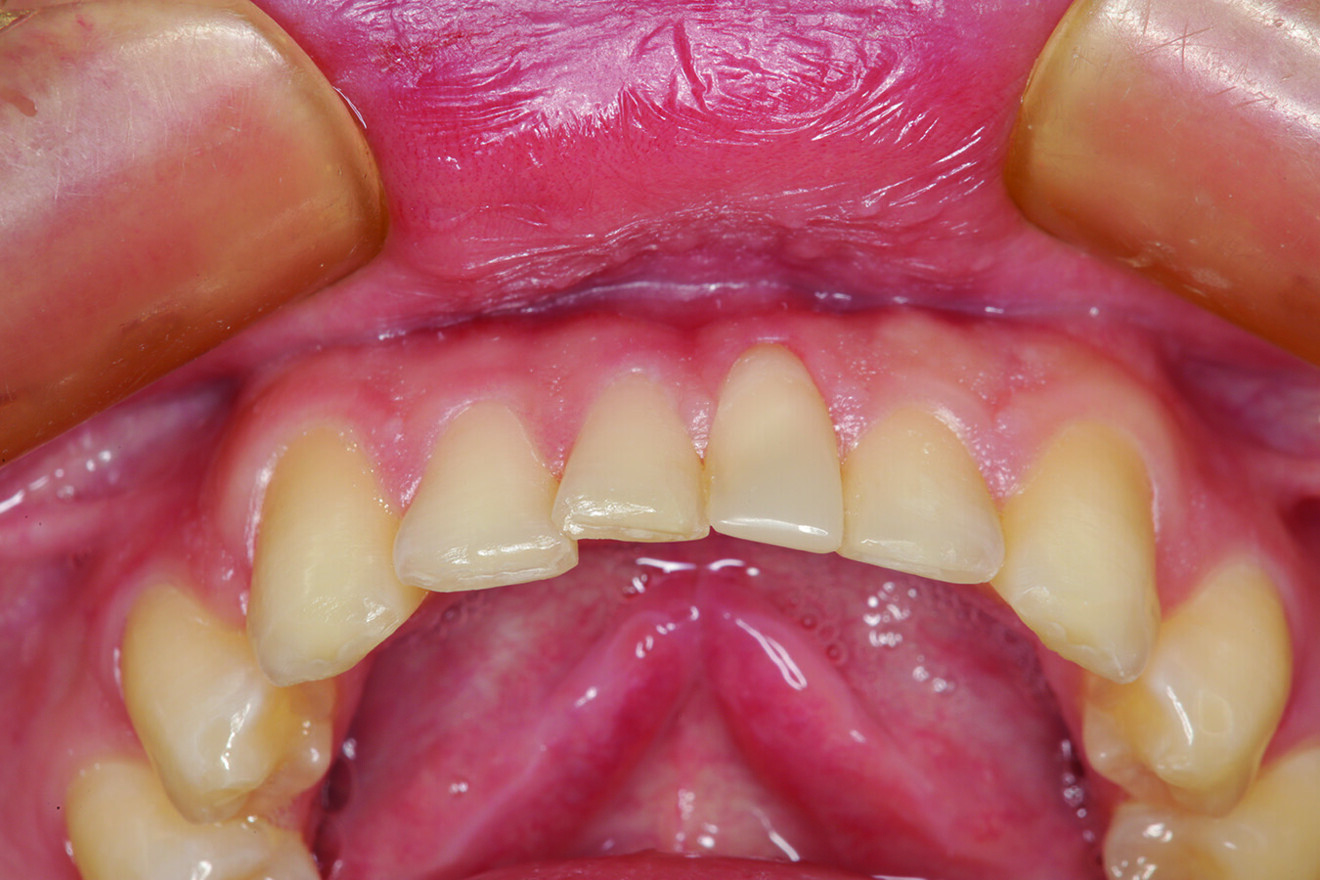

Fig. 2: Teeth in protrusive excursion, showing excessive wear on the tooth (# 41) opposing tooth #11, indicating hyperfunction and increased functional stress on the restored area.

What about the alignment of the opposing teeth? It could be observed that excessive wear was present on the incisal edges of teeth #31 and 41 (Fig. 2). From the incisal view, exten­sive wear was seen on all mandibular inci­sal edges due to occlusal disease—which is often seen yet left untreated (Fig. 3). Tooth #41 was also facially positioned so that in pro­trusive excursion it engaged the palatal surface of tooth #11 prematurely, placing addi­tional stress on both the palatal surface and inci­sal edge of tooth #11 before coupling with the remainder of the maxillary anterior segment. This demonstrates that addressing these issues restoratively involves more than just fixing a chipped composite restoration.